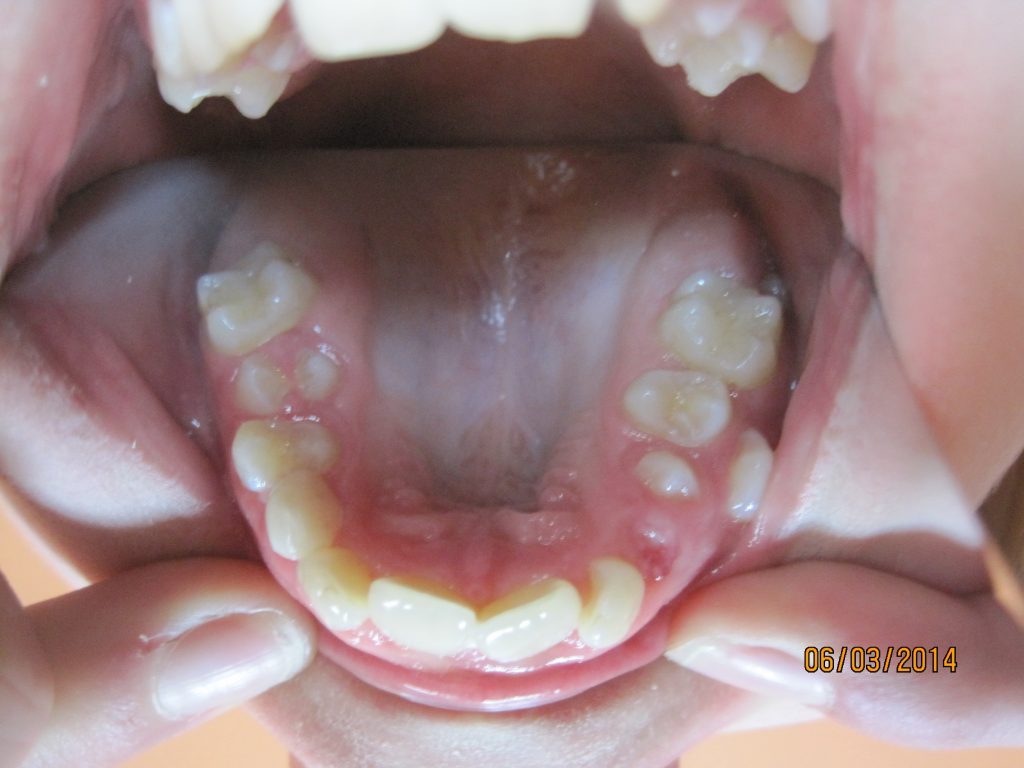

Streszczenie: W pracy opisano rodzaje klasyfikacji zaburzenia i sposób postępowania na przykładzie własnego przypadku klinicznego. Zwrócono uwagę na właściwą diagnostykę radiologiczną (panorama, zdjęcie zgryzowe i tomografia komputerowa), która pozwala na określenie lokalizacji zębów, stosunku do struktur sąsiednich, a zastosowana odpowiednio wcześnie pozwala zapobiec nasileniu nieprawidłowości. W prezentowanym przypadku klinicznym w ocenie lekarza i pacjenta uzyskano satysfakcjonujący estetyczny i czynnościowy wynik leczenia, niewymagający korekty kształtu zębów i zabiegów periodontologicznych.

Summary: The paper describes the classification of the disorder and the procedure on the basis of our own clinical case. Attention is drawn to the proper radiological diagnostics (panorama, occlusal image, and computer tomography) which permits to define the location of the teeth, the relation to the adjacent structures and, if performed early enough, allows also to avoid the progress of the anomaly. In the presented clinical case, in the doctor’s and the patient’s respective opinion, the result was satisfactory both on the aesthetic and practical level; it did not require the correction of the shape of the teeth or any [...]